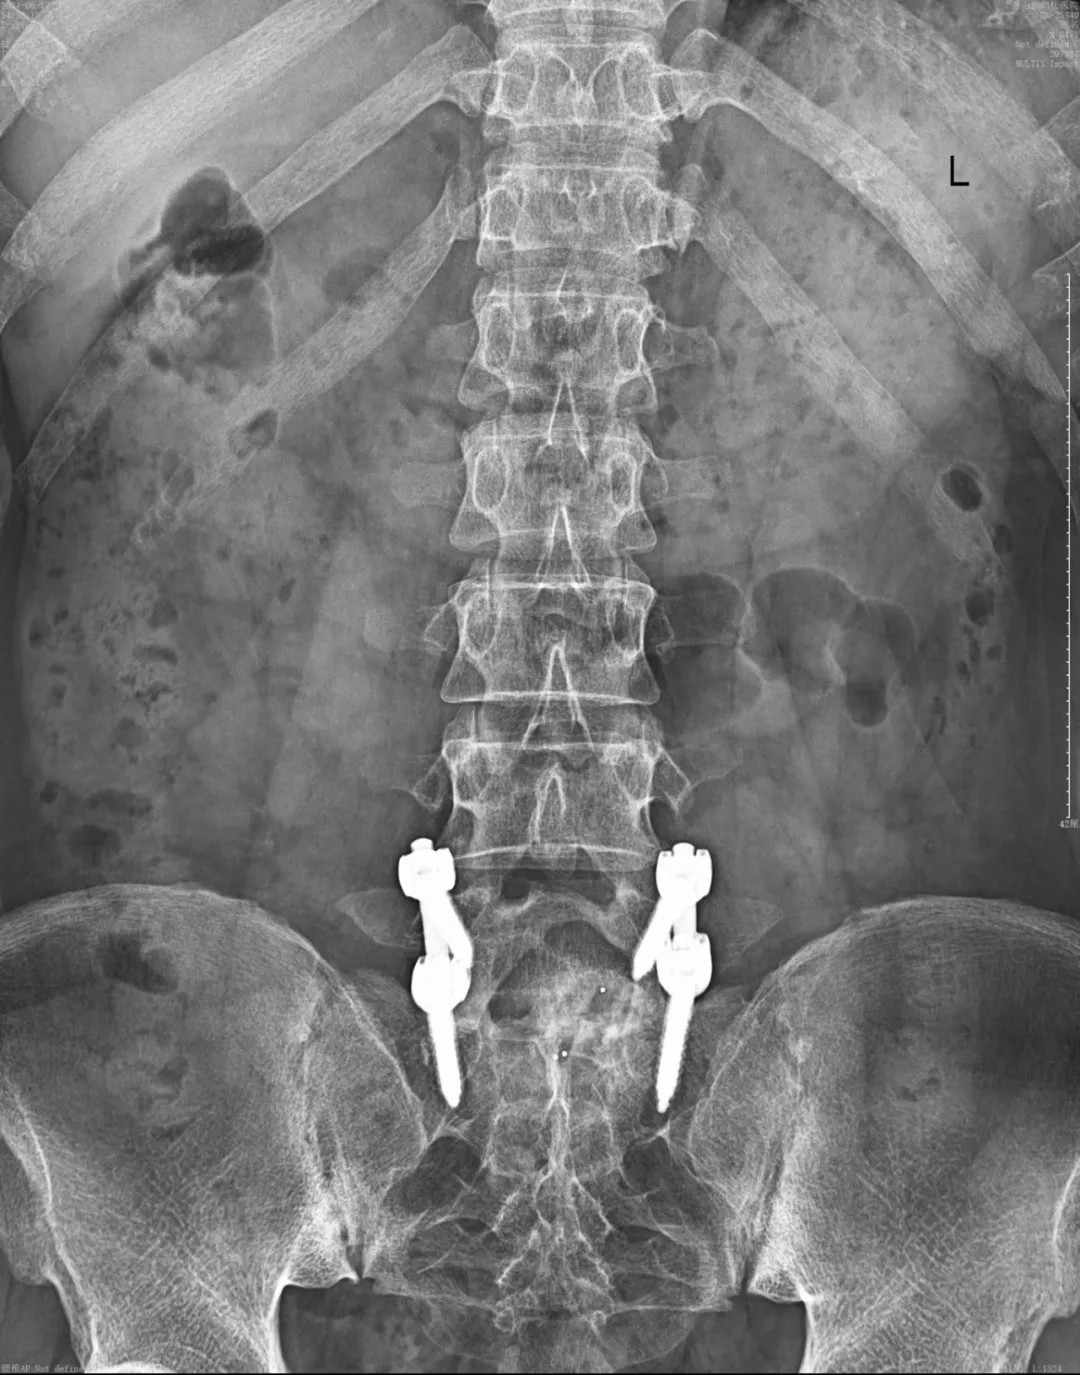

針對患者復(fù)雜的病情及二次翻修手術(shù)的情況,我院專家團(tuán)隊(duì)?wèi){借豐富的經(jīng)驗(yàn)、專業(yè)的技術(shù)、密切的配合,為患者在蔡司TIVATO 700手術(shù)顯微鏡下實(shí)施了腰椎融合術(shù)后翻修、融合內(nèi)固定微創(chuàng)手術(shù)。

手術(shù)全程使用術(shù)中電生理監(jiān)測系統(tǒng),每步都力求精準(zhǔn)細(xì)致。在解除原有問題的同時(shí),一定程度保護(hù)了周圍正常組織。經(jīng)過數(shù)小時(shí)的緊張操作,手術(shù)圓滿成功。